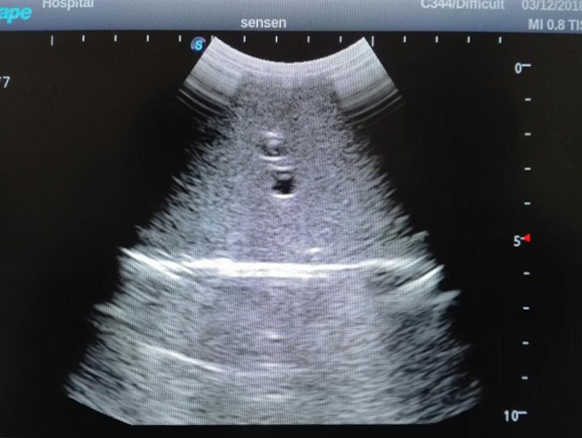

4)  ltrasound gallbladder pathologies like cholecystitis, gallstone and polypoid degeneration

5)  Normal & pathological ultrasound live and intestine models inside